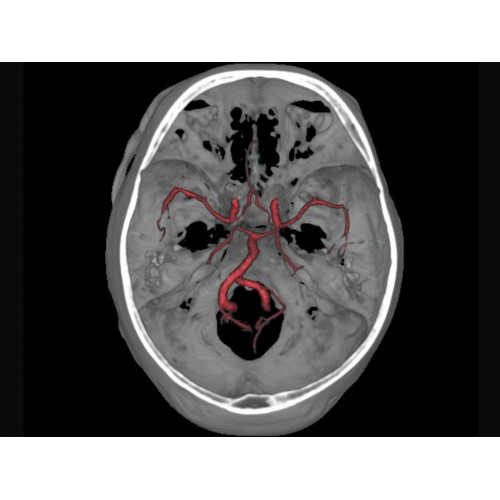

Позволяет проводить комплексные исследования всех анатомических зон, включая нейровизуализацию, ангиографию, исследования органов грудной и брюшной полости. Особенно эффективен для раннего выявления онкологических заболеваний.

Специализированные исследования